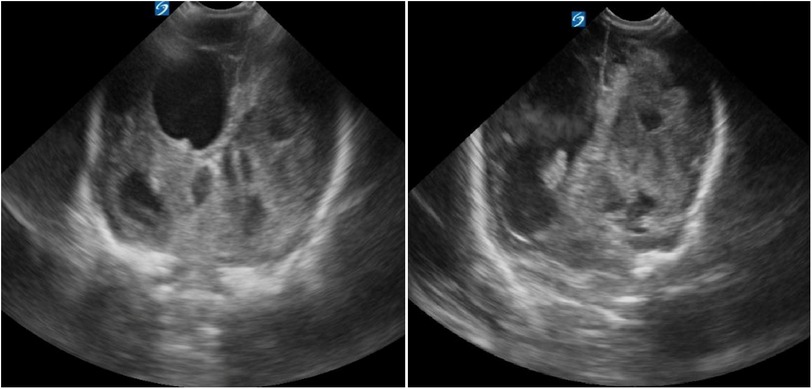

ABSTRACT Background: Congenital syphilis (CS) remains a global public health concern, with rising incidence even in high-income countries. In Italy, a higher risk has been reported among primigravidae and younger mothers with late or missed prenatal screening. While neurological involvement in CS is well known, it is rarely reported in preterm infants, where it may be severe and atypical. Case Presentation A male preterm infant, delivered at 32 weeks via emergency cesarean due to abnormal fetal monitoring and breech position, was admitted to our NICU with intraventricular hemorrhage, midline shift, and hydrocephalus, requiring neurosurgery. He later developed a metaphyseal bone lesion; Staphylococcus aureus was found in blood cultures. Despite antibiotics, persistent thrombocytopenia and infectious symptoms led to further testing, revealing congenital syphilis with neurological involvement and osteomyelitis and osteochondritis of the distal ulna and radio from an undetected maternal treponemal infection during pregnancy. Penicillin therapy produced slow recovery, but the newborn developed epilepsy and spastic tetraplegia by 24 months. Genetic and metabolic tests were negative. Literature review rarely shows similar CS cases, especially in preterm infants. Conclusion: This case highlights the relevance of universal maternal syphilis screening and early neonatal evaluation. Maternal Treponema pallidum infection during pregnancy can result in preterm birth and may be associated with neurological complications, such as hemorrhages, seizures, and motor impairment, which can require multidisciplinary management and long-term follow-up.